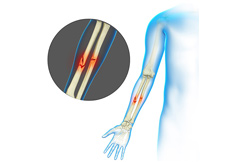

What are Forearm Fractures?

The forearm is made up of 2 bones, namely, the radius and ulna. The primary function of your forearm is rotation i.e., the ability to turn your palm up and down. The fracture of the forearm affects the ability to rotate your arm, as well as bend and straighten the wrist and elbow. The breaking of the radius or ulna in the middle of the bone requires a strong force and is most commonly seen in adults. In most of the cases, both bones are broken during a forearm fracture.

The symptoms of a forearm fracture include intense pain in the arm, bruising and swelling. Your fractured forearm may appear bent and shorter compared to your other arm. You may experience numbness or weakness in the fingers and wrist. You may be unable to rotate your arm. Sometimes, a broken bone sticks out through the skin or the wound penetrates down to the broken bone.